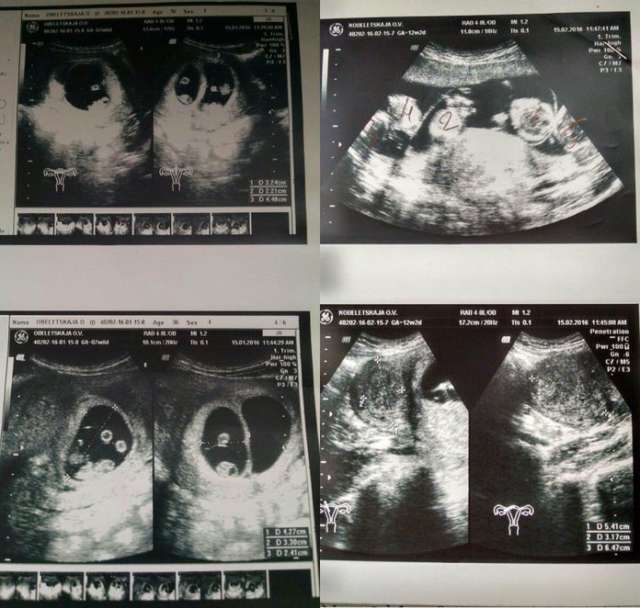

Սակայն այն, ինչ պետք է լիներ ընտանեկան իրադարձություն, վերածվեց համաշխարհային սենսացիայի: Երբ կինը գնաց հերթական բուժզննման, բժիշկները նրան հայտնեցին շոկային լուրը: Ուլտրաձայնային հետազոտությունը ցույց էր տվել, որ կինը հնգյակ պետք է ունենա:

Առանց արհեստական բեղմնավորման հնգյակ ունենալը հազվադեպ երևույթ է, որը պատահում է 55 միլիոնից 1-ի մոտ: